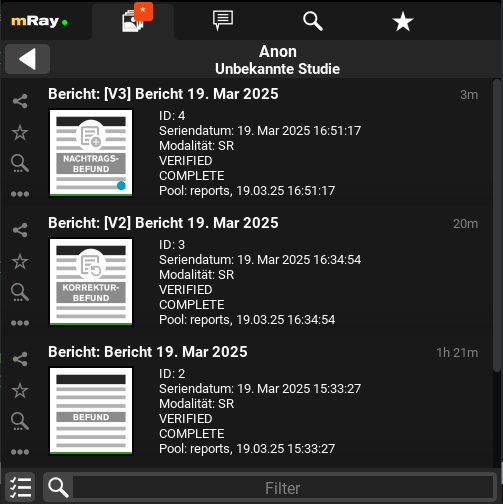

12.6.3. Befundverlauf

Korrektur- und Nachtragsbefunde enthalten ein Verlauf von vorherigen Versionen. Diese Versionen können in der Serienansicht einer Studie eingesehen werden. Um in diese zu gelangen, siehe Serienauswahl.